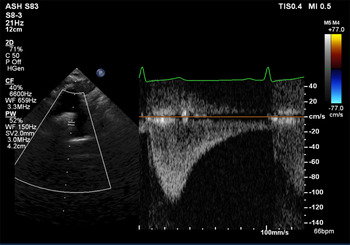

Aortic arch contour was abnormal and appeared to taper at the isthmus. Doppler velocity at the isthmus was within normal limits (1.1 m/s), but a pathologic flow profile with continuation through diastole was noted (Fig 1). Lack of pulsatility and low-velocity continuous flow was found on abdominal descending aorta interrogation (Fig 2). Exam revealed the absence of distal pulses and upper extremity hypertension (139/87 mmHg) with a significant gradient to the lower extremity (72/48 mmHg). CT angiogram confirmed the suspected diagnosis of coarctation of the aorta (Fig 3) and showed extensive vertebral collateralisation supplying the descending aorta. He underwent successful surgical coarctectomy with a lumenal diameter of the excised aortic isthmus found to be less than 1 mm diameter (Fig 4).

Figure 1. Pathologic Doppler profile in the distal aortic arch showing a “diastolic tail” – flow continuation through diastole. Peak velocity (1.1 m/s) is within the normal range.

We often grade the severity of obstruction by reporting Doppler-derived pressure gradients, and high-velocity flow through the isthmus is expected in severe coarctation. But, a basic tenet of echocardiography is that flow is required to produce a high gradient. When the coarctation has been longstanding and severe, the presence of collateral flow through the vertebral arteries may diminish flow across the coarctation and the Doppler-derived gradient may be less severe than expected for the degree of obstruction.Reference Houston, Simpson, Pollock, Jamieson, Doig and Coleman3 This case elegantly highlights the significance of Doppler flow profile in making the diagnosis – tracings with continuous antegrade diastolic flow in the arch and low amplitude continuous undulating flow in the abdominal descending aorta are pathologic, and provide important indirect evidence for aortic coarctation.Reference Dijkema, Leiner and Grotenhuis1,2,Reference Shaddy, Snider, Silverman and Lutin4–Reference Doshi and Chikkabyrappa6